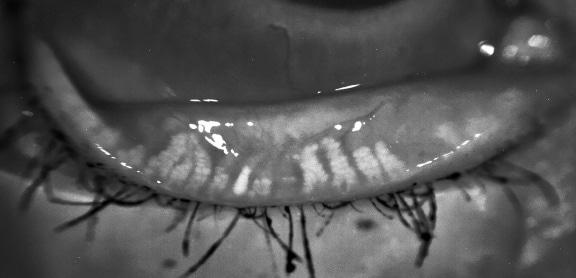

Stade 2

Entre 33% et 66% des glandes atrophiées

– Dilatation et bouchons présents